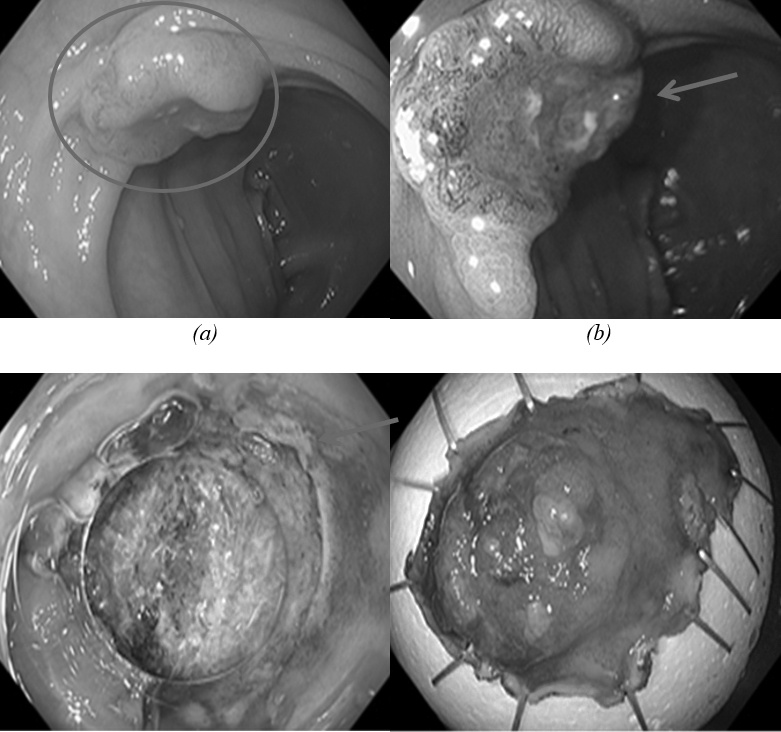

Các bác sĩ chỉ định phẫu thuật nội soi cắt tách dưới niêm mạc, một phương pháp điều trị tiên tiến giúp loại bỏ khối u triệt để mà vẫn bảo tồn tối đa chức năng cơ quan tiêu hóa.

Ca phẫu thuật diễn ra thuận lợi, khối u được bóc tách và lấy trọn qua nội soi. Sau mổ, bệnh nhân hồi phục tốt, ăn uống bình thường, kết quả tái khám cho thấy không còn tổn thương ác tính. Ông T. được xuất viện trong tình trạng ổn định.

Hình ảnh tổn thương ở đại tràng của bệnh nhân. Ảnh: BVCC.